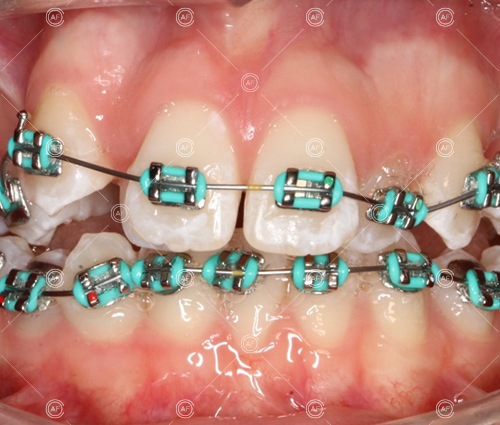

Treatment progressed by starting with thin, flexible nickel titanium archwires of a round diameter, transitioning to a rectangular nickel titanium archwire before eventually working up to a working archwire (1925 stainless steel).

Residual space from the extractions were closed using upper and lower nickel titanium closing coils. Class 2 elastics were used to facilitate space closure in order to gain class 1 buccal segments.

MH debonded in December 2020, with overall treatment time of around 14 months.